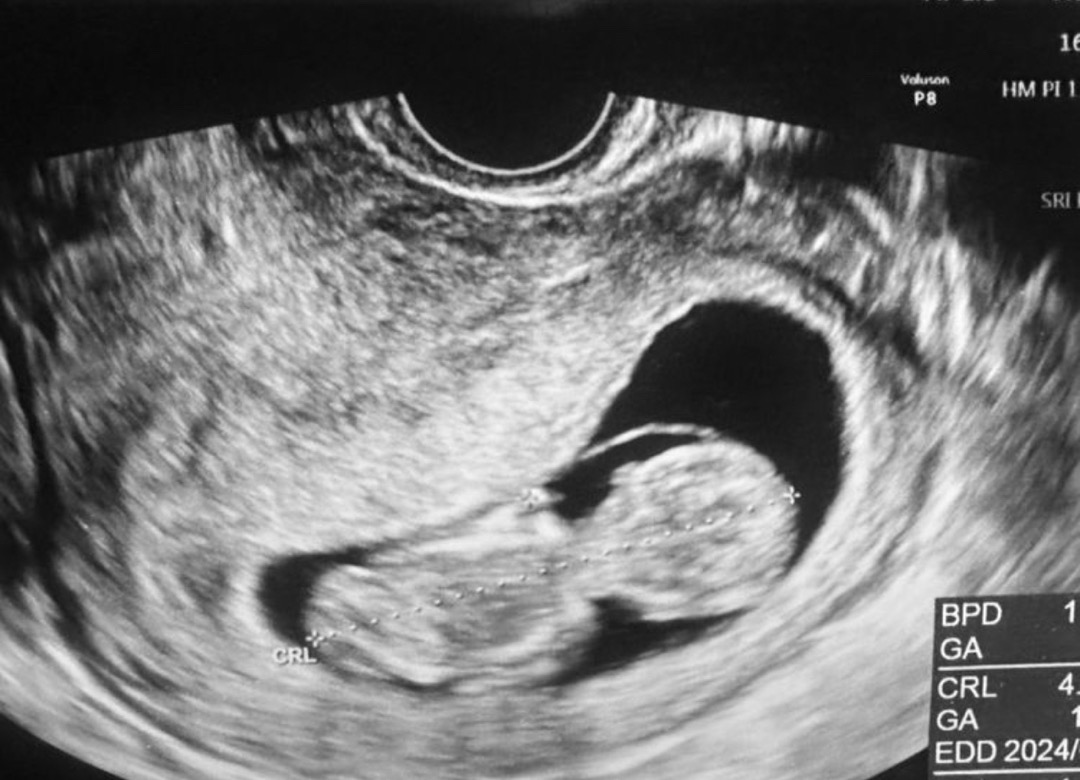

10주 6일차 아랫배 알배기는 듯한 느낌

어제밤에 갑자기 누워있다가 재채기하면서 아랫배 힘이 들어갔더니 복근생기는것처럼 뭔가 알배기는 느낌이 아랫배에들고 아침에 화징실가서도 그런 느낌이 들어서 병원갔는데 자궁이 커지면서 그럴수 있다고하네요 전날 무가운걸 좀들었는데 그러면서 배에 힘이 들어가서 그런거라고 ..다행이 잘크고 있는거 봐서 안심 ! 엄청커서 깜짝놀랐어요! 지난주에는 젤리곰이였는데 어느새 사람느낌이 ㅎㅎ 아직 주변에 알리지않아서 요기다 자랑해봐영 😍

어맛! 목 부분도 보이는 것 같아서 진짜 신기해요! 아가가 잘 있어서 정말 기분 좋으시겠어요. ㅠㅠ 만나는 날까지 건강하길 응원합니다!! 순산하세요. 🫶